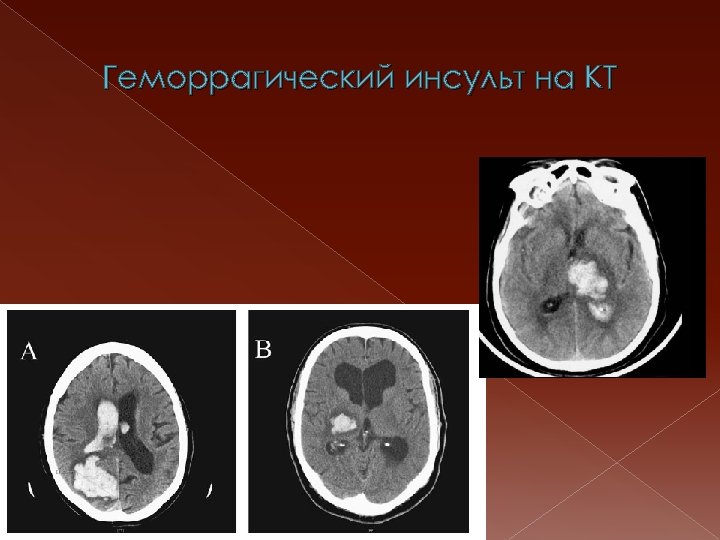

Геморрагический инсульт на КТ